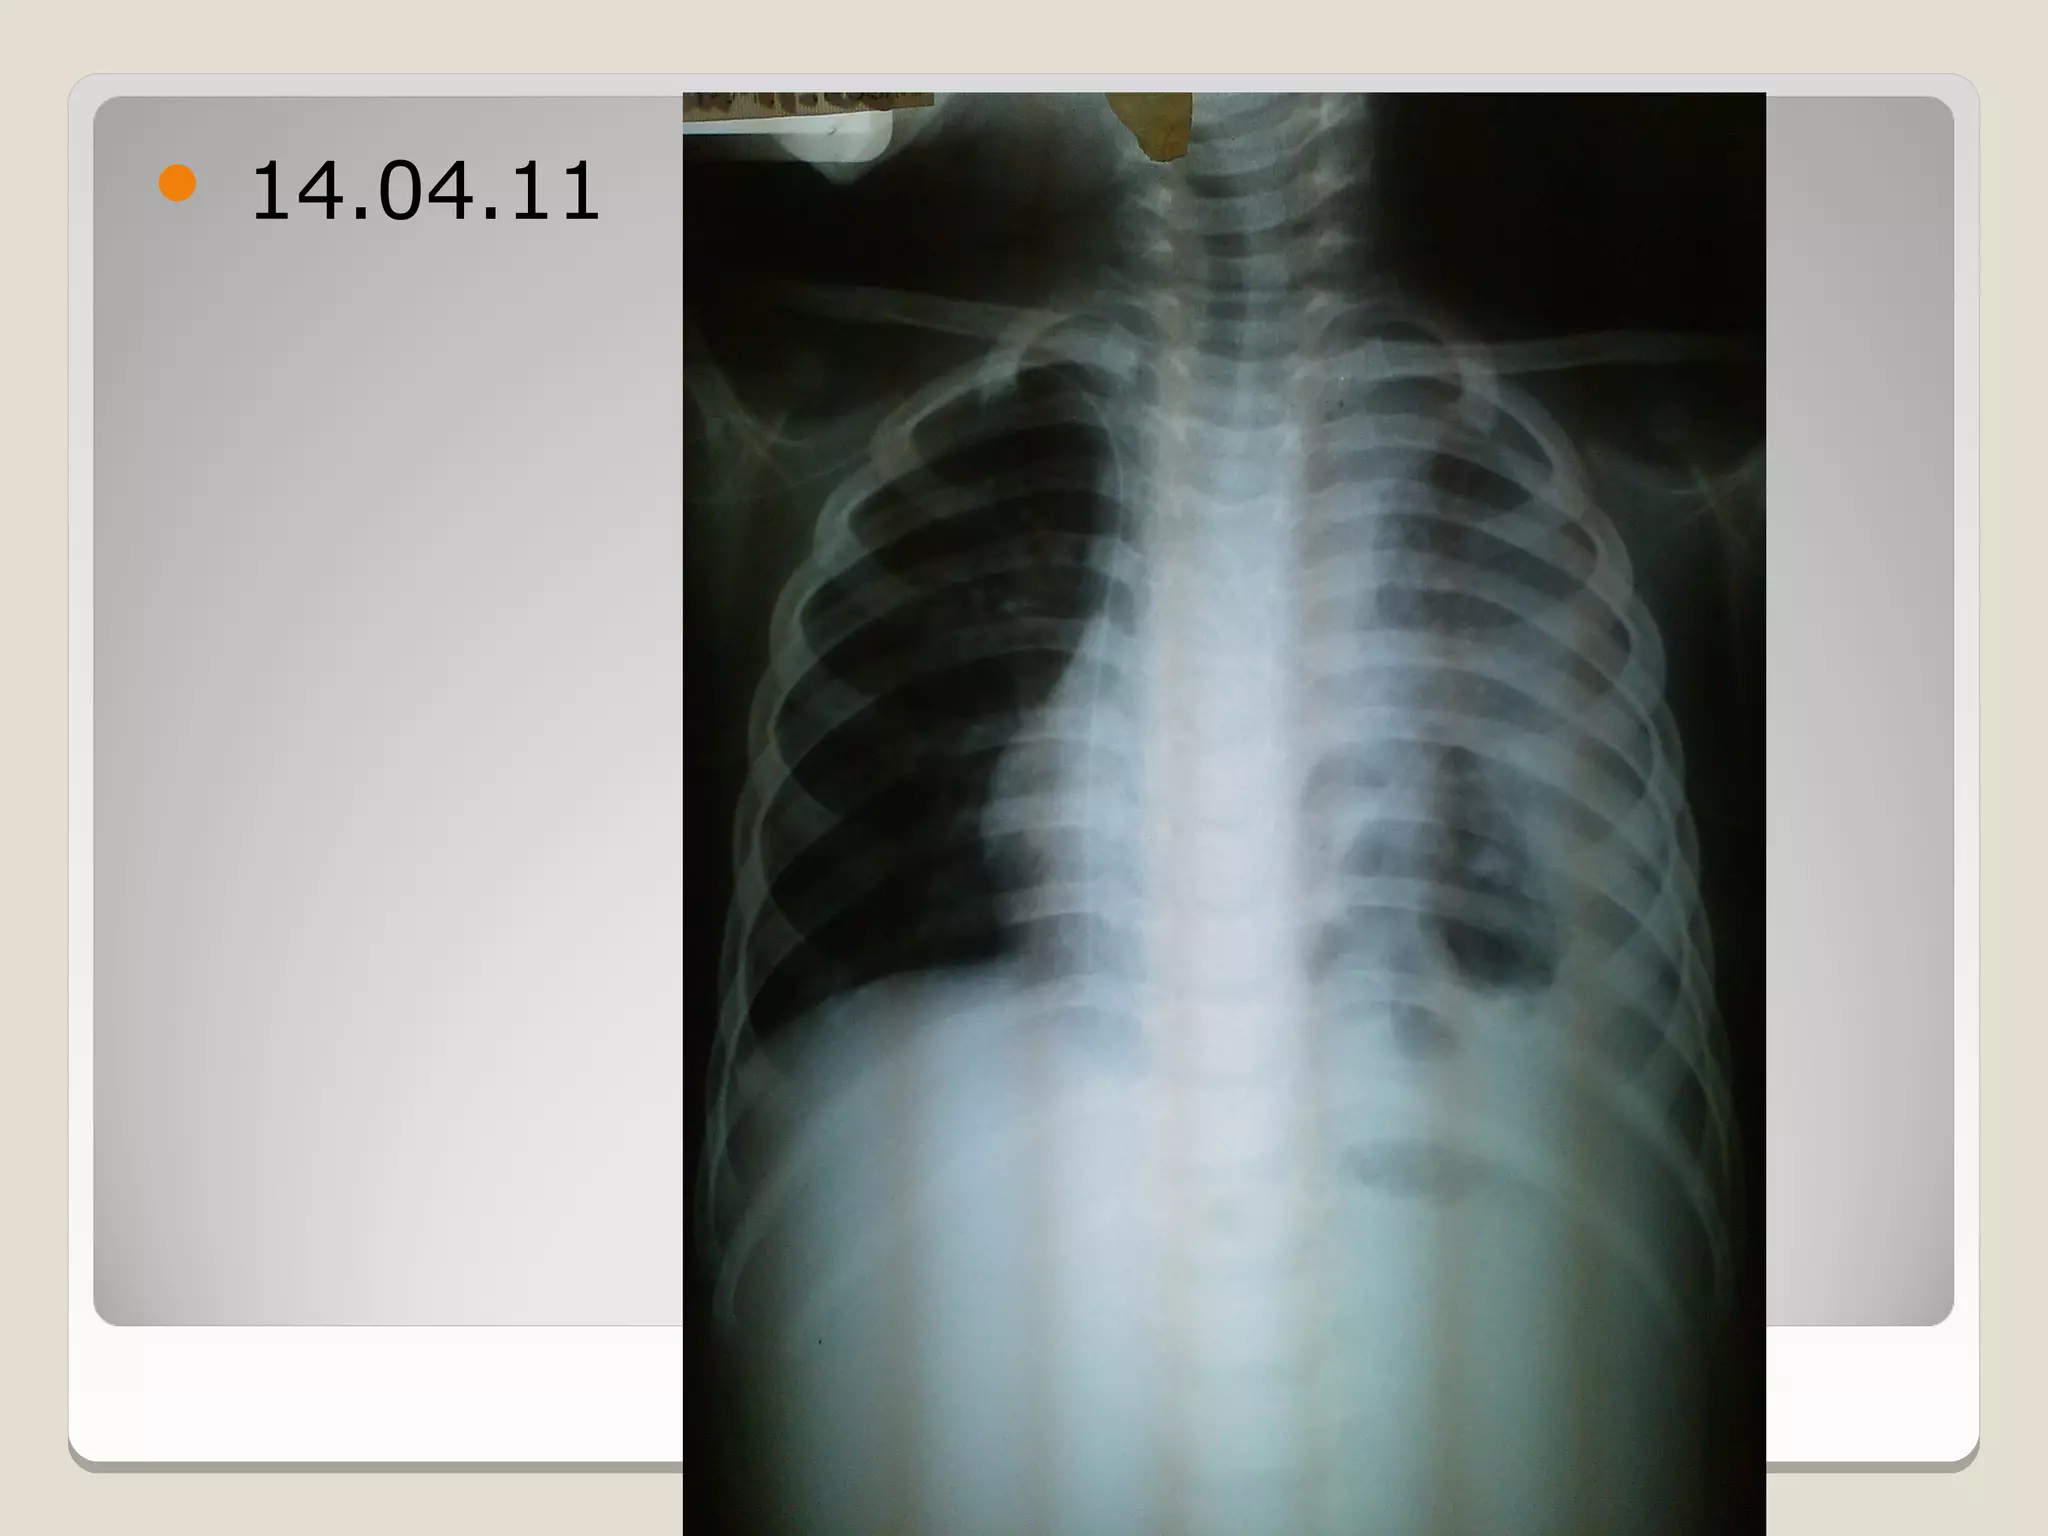

   14.04.11

14.04.11